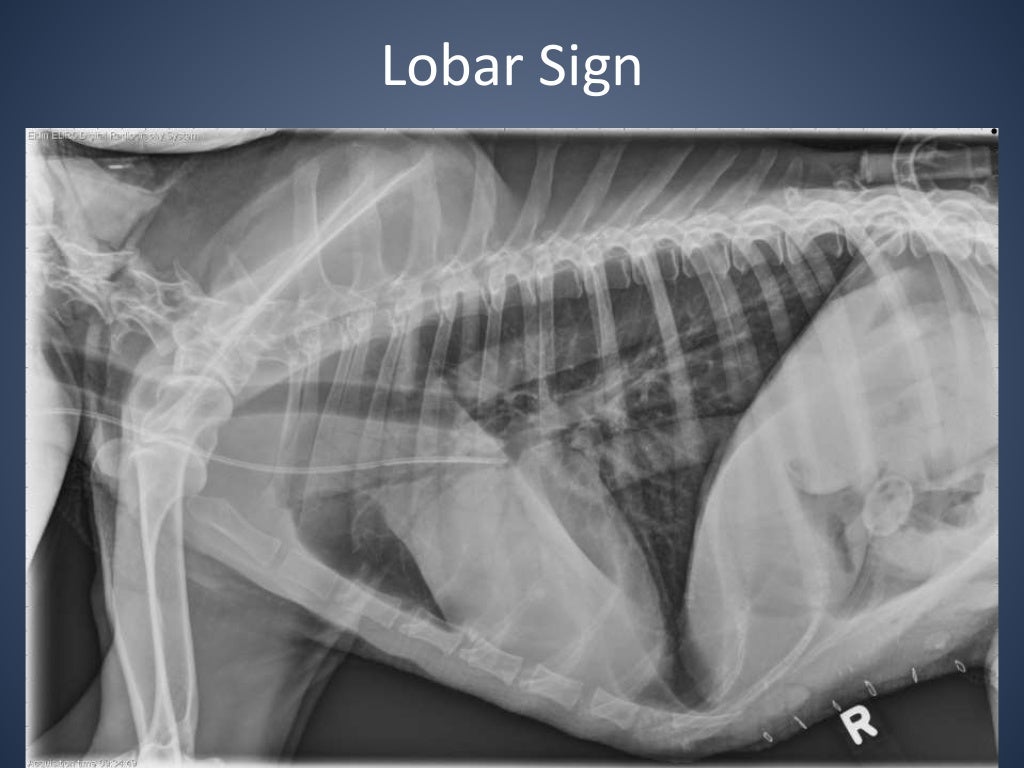

From www.slideshare.net

The Radiographic Approach to the Coughing Dog Kennel Cough Xray The prominent clinical sign of kennel cough is a cough that sounds like a goose honk that may be followed by retching and gagging. The classic symptom of kennel cough is a persistent, forceful cough. Learn about the veterinary topic of kennel cough (infectious tracheobronchitis) in dogs. Signs of systemic illness (eg, lethargy, decreased appetite). In a coughing pet, the. Kennel Cough Xray.